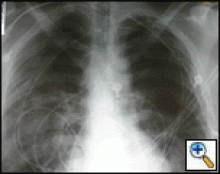

| Figure 1: Computed tomography showing a typical right upper lobe lung lesion. surrounded by lung parenchyma suitable for VATS lobectomy |

VATS lobectomies are performed on patients with clinical stage I lung cancer assessed by computed tomography (CT) and positron emission tomography (PET). The procedure is usually performed for tumors less than 4 cm in maximum diameter, but we have resected tumors as large as 6.5 cm. This procedure can be performed regardless of tumor location within the lobe; however, procedures on very proximal hilar tumors are converted to open thoracotomy for better assessment whenever pneumonectomy is contemplated. Current contraindications to performing this procedure include chest wall involvement or surgery planned after neoadjuvant chemotherapy for N2 disease. Prior thoracotomy is not an absolute contraindication since the degree of adhesions and the ability to mobilize the lung adequately will vary among patients. The degree of emphysema, comorbidities, and age are not contraindications, and patients so affected are not managed differently than patients undergoing standard thoracotomy. Figure 1 demonstrates a computed tomography of the typical lesion that is amenable to VATS lobectomy.